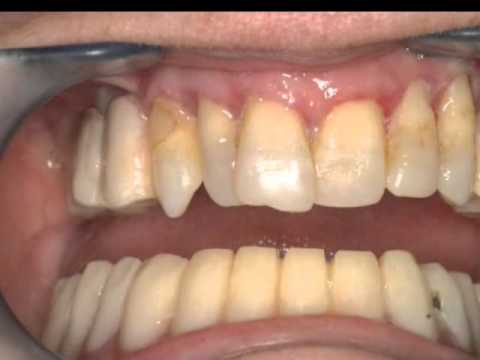

Desde hace 25 años , fuimos pioneros en nuestro pais en aplicar implantes en rehabilitaciones de pacientes con implantes dentales, miles de pacientes disfrutan desde entonces de estos avances. Nuestros trabajos han sido premiados en congresos internacionales de la especialidad, diseñamos una técnica denominada Esbipro e inventamos unos instrumentos, los expansores roscados de hueso, para poder insertar implantes en condiciones donde no era pposible insertar implantes. Nuestros trabajos han sido publicados por dos de las sociedades científicas más reconocidas mundialmente, la Asociación Norteamericana de cirugía maxilofacial y la Asociación Norteamericana de disfunción craneomandibular. Todos los avances que se han venido produciendo en nuestra especialidad se ha ido incorporando a nuestra praxis, Microscopio, Láser, RESONANCIA CUANTICA MOLECULAR, cirugía ósea piezoelectrica, Gás de la Risa,Esterilización ciclo B,Panorámica digital y TAC.